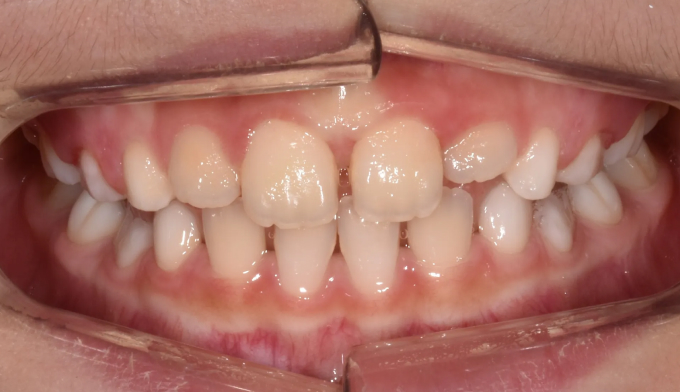

구강내 사진만 확인하였을때는 앞니가 거꾸로 물리는 반대교합이 심해 주걱턱 경향도 심할것으로 예상됩니다.

하지만 엑스레이 분석시 주걱턱 수치는 정상수치에 가깝습니다.

이런 경우 무리하게 성장교정을 진행하기 보다는 거꾸로 물리는 앞니만 간단히 넘겨주는 치료만으로도 충분합니다. 프리올소와 같은 근기능장치를 이용하여 3,4개월이면 금세 반대교합이 해소됩니다.